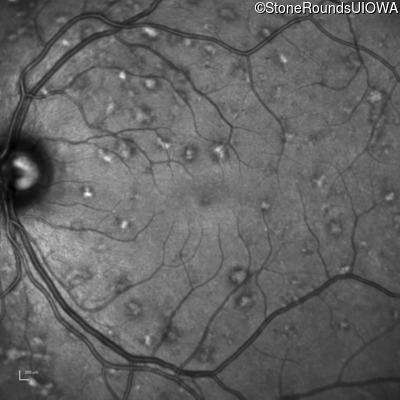

AR Stargardt Disease (IIA)

Age at visit: 30 years

This 30 year old asymptomatic man had fundus abnormalities identified incidentally on a routine exam.

Diagnosis & molecular findings

Disease Gene Allele 1 variant(s) Allele 2 variant(s) Inheritance mode

AR Stargardt Disease ABCA4 IVS30+1321 A>G Asn965Ser AAT>AGT AR